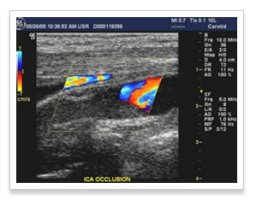

경동맥초음파

경동맥 초음파 검사로 알수있는병 대동맥 초음파 갑상선 초음파 경동맥 초음파 검사비용 동맥경화 검사 저선량 흉부ct 전립선 초음파 경동맥 초음파 검사 관상동맥 ct 경동맥 두께 경동맥 협착증 경동맥 초음파 검사2mm경화증 경동맥초음파 비용 골반초음파 대구 경동맥초음파 동맥경화 폐ct 대장내시경